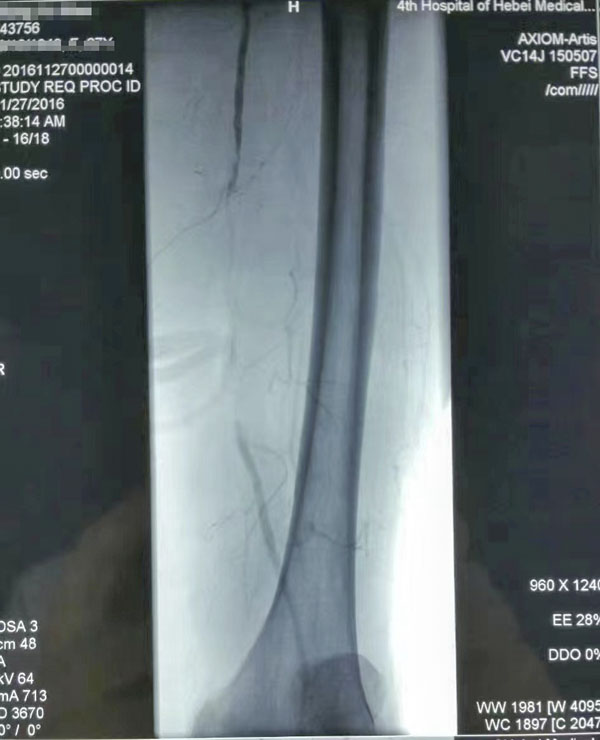

介入治疗前后对比

糖尿病足重在预防,而预防和治疗下肢血管病变是防治糖尿病足的有效措施。下肢血运重建是糖尿病下肢血管病变治疗的根本,采用球囊扩张开通狭窄或闭塞的下肢动脉(介入治疗),恢复直达足部的血流,是治疗糖尿病下肢血管病变的根本措施,具有立竿见影的效果。这也是近年来在糖尿病足诊治方面取得的又一新进展,为广大糖尿病下肢血管病变患者解除了痛苦,使糖尿病足患者截肢率由34%降至4%。世界防治糖尿病日到来之际,希望广大糖尿病患者关注糖尿病下肢血管病变,保护自己的双足,做到早发现、早治疗,提升幸福感,快乐每一天。